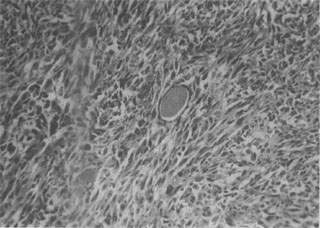

图7-17 纤维肉

细胞呈梭形,体积较大,核大,核分裂像较多,具明显的异型性